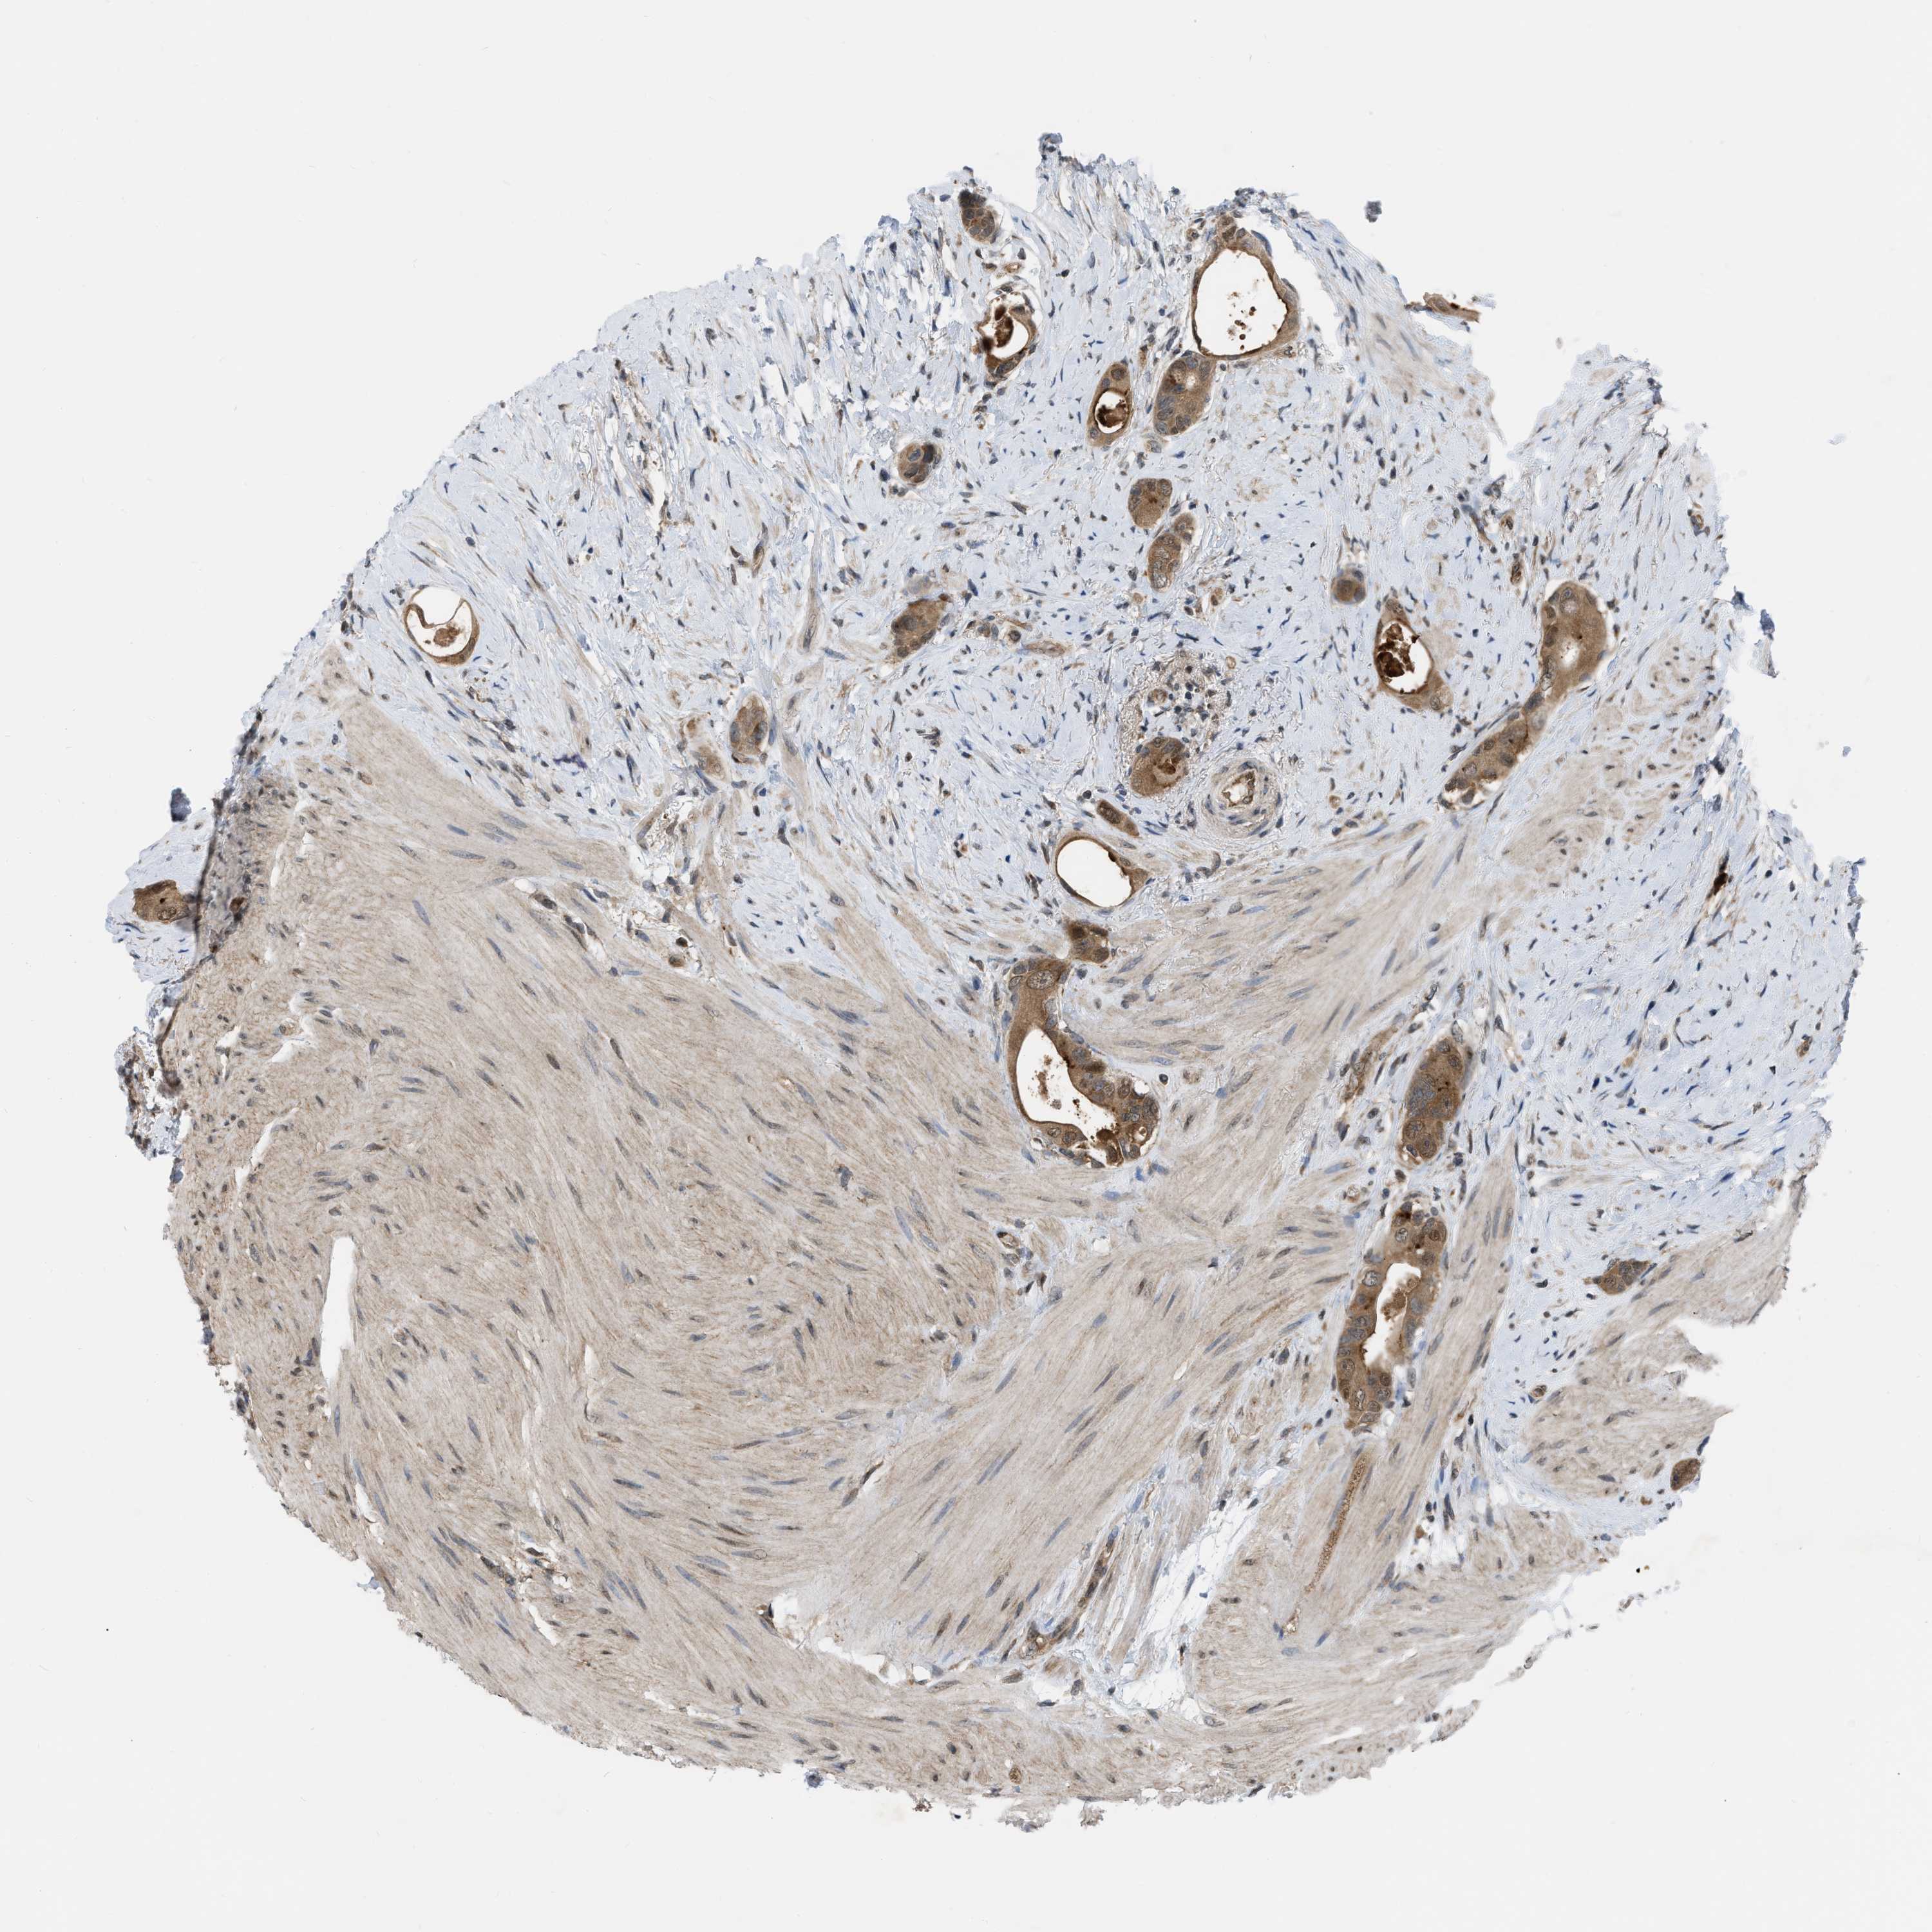

CANCER COLORECTAL CANCER Show tissue menu

Colorectal cancer

Human cancer

Colon adenocarcinoma

Rectum adenocarcinoma